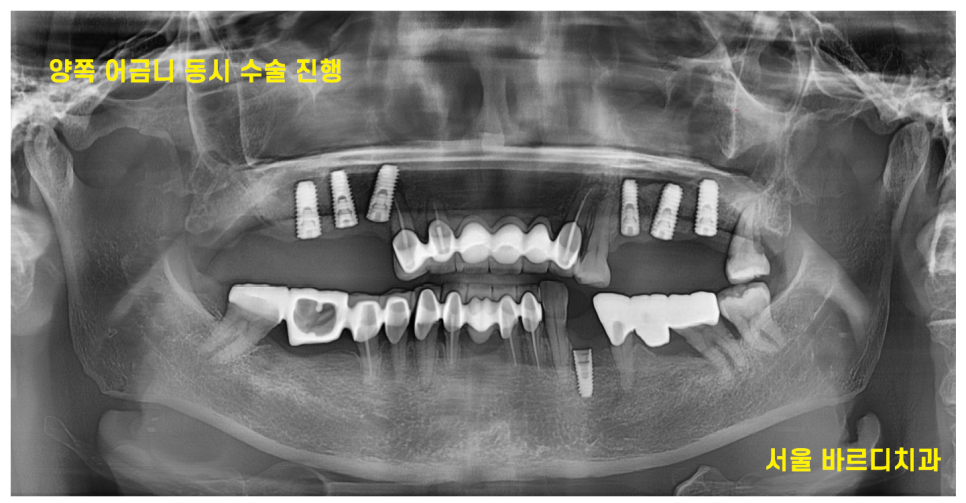

231021

우선 문제가 되는 양쪽 브릿지 발치를 진행

잇몸뼈가 없다보니 발치와 동시에 뼈이식을 진행하였습니다.

발치 당일에 임플란트를 심을 수 없어

뼈이식부터 해놓고

치유를 기다린거죠~

그리고 지속 체크를 하였고 약 2달 뒤

네비게이션 임플란트 방식을 통해

수술을 진행하기로 하였습니다.

양쪽 어금니 임플란트 동시에 하기로 하였거든요.

231023

네비게이션은 미리 수술을 예측해볼 수 있고

정확도와 안전성이 높아

이렇게 수술 개수가 많고

난이도가 많은 경우 추천 드리고 있답니다~

231031

날 잡고 양쪽 어금니 임플란트 동시에

아래 상실된 부분까지 식립하여

총 7개의 임플란트를 하루에 심었습니다.

잇몸뼈가 많이 없어서

1)발치 당일 뼈이식 한번

- 수술 당일 뼈이식 한번

총 2번의 뼈이식을 진행